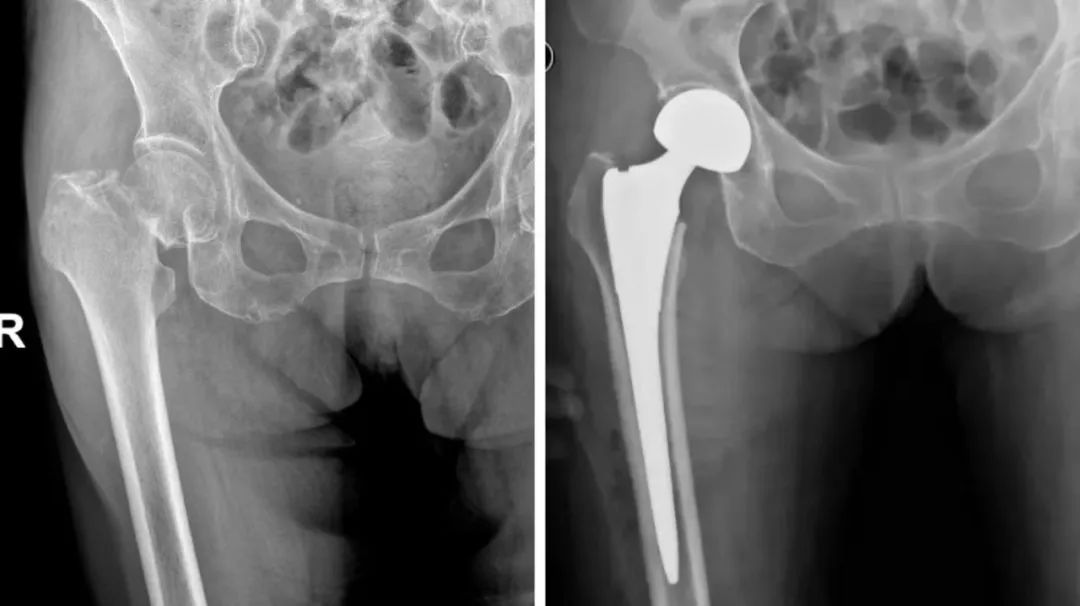

术前与术后影像资料

伍主任详细询问病史并结合影像学检查,股骨头已经明显的变形,呈现出塌陷变扁的状态,髋臼边缘的骨质也出现了硬化现象,明确诊断为“右侧酒精性股骨头坏死”,股骨头坏死塌陷,需要施行人工髋关节置换术。早治疗早恢复,患者入院后,完善术前相关检查,排除了手术禁忌。